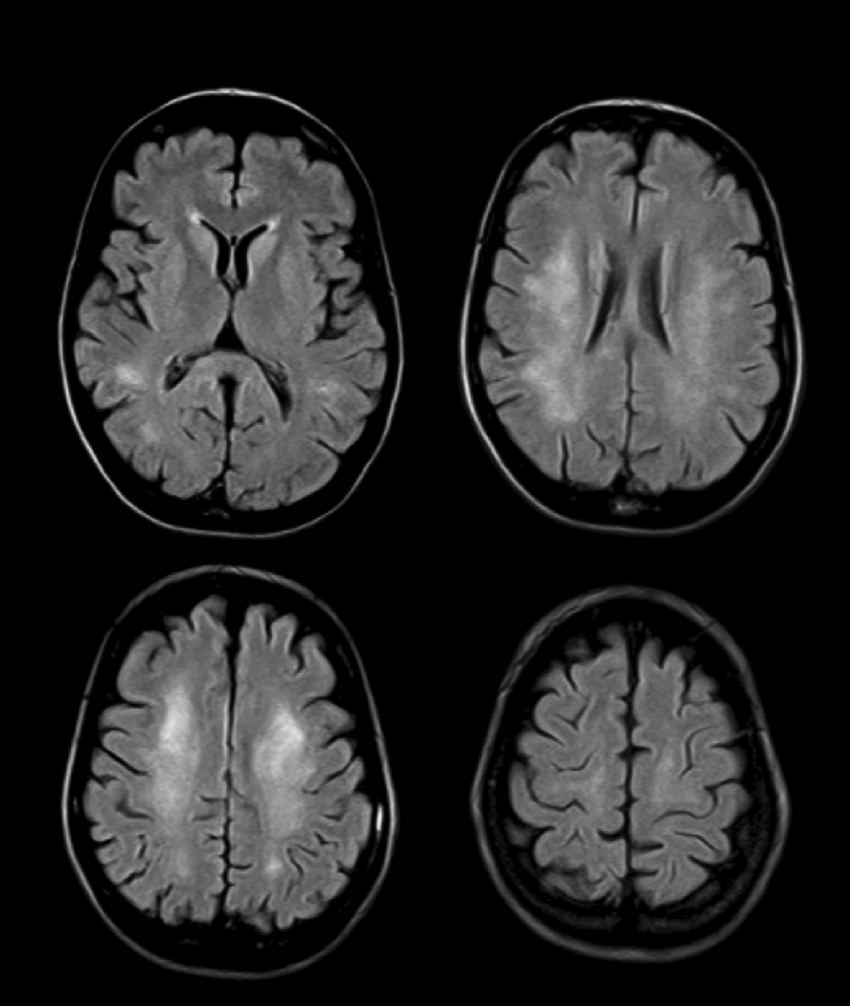

Magnetic Reasonance Imaging

Magnetic resonance imaging (MRI) uses magnetic field gradients to create images showing both anatomy and physiological activity.